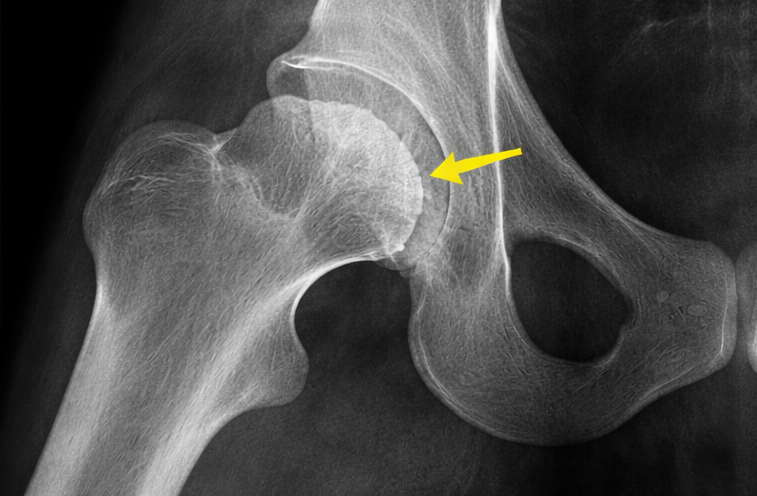

Avascular necrosis (AVN) of the head of femur is a progressive orthopedic condition characterized by compromised blood supply to the femoral head, leading to bone ischemia, structural collapse, and secondary osteoarthritis if untreated. It commonly affects young and middle-aged adults and is associated with risk factors such as corticosteroid use, alcohol abuse, trauma, and certain systemic diseases. Clinical presentation ranges from asymptomatic early disease to severe hip pain and functional limitation in advanced stages. Diagnosis relies on clinical suspicion supported by imaging, with magnetic resonance imaging (MRI) being the gold standard for early detection. Management strategies depend on disease stage and include conservative measures, pharmacologic therapy, joint-preserving surgical procedures, and total hip arthroplasty in advanced cases. This case report describes a young patient with avascular necrosis of the femoral head, highlighting clinical features, diagnostic evaluation, management, and short-term outcomes. Early diagnosis and timely intervention are essential to delay disease progression and preserve joint function.

MRI is the most sensitive modality for early diagnosis, allowing detection before radiographic changes become evident. Early-stage disease can be managed with conservative and joint-preserving surgical techniques such as core decompression, which aims to restore blood flow and delay disease progression. Advanced stages often require total hip arthroplasty, which is less desirable in young patients due to implant longevity concerns.